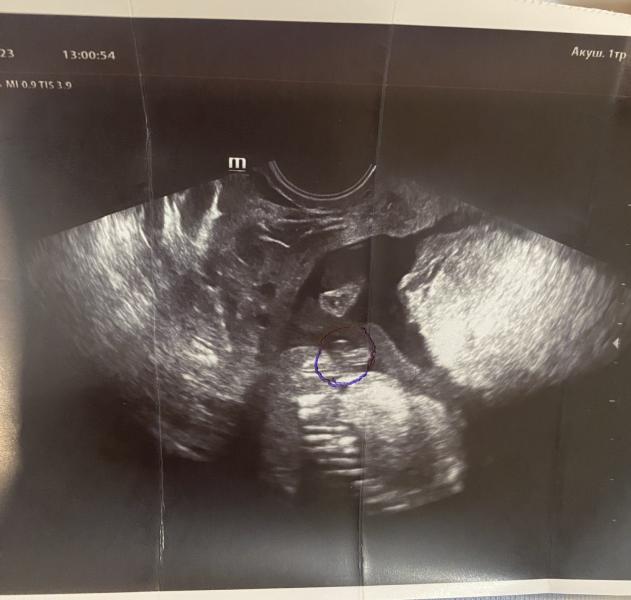

Нужна помощь. Попросила врача-узи посмотреть пол, она в конверт положила это. То что она обвела похоже на орган мальчика, но сам снимок че то вообще не понятно. Откуда этот орган и куда😂 помогитеееее

Есть ощущения, что это вид сверху малыша, потому что смотрели вагинально. Через живот вообще не понятно было, ноги скрестил

Мальчик) у девочки бы не был такой большой клитор на таком сроке🙈

да вроде прям явно пацан)